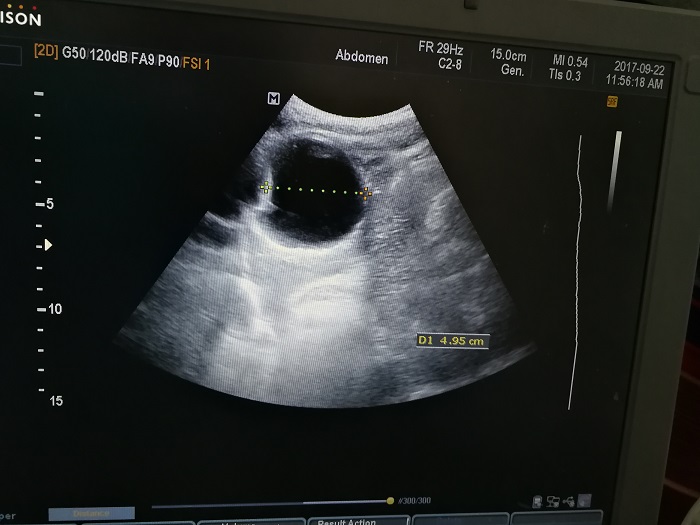

扎西(化名),男,15歲,包蟲病篩查陽(yáng)性,牧區(qū)孩子,家里有牦牛20頭、羊200只,狗1條,牛羊自家屠宰,飲用河水。

●革吉縣初級(jí)中學(xué)篩查點(diǎn) · B超現(xiàn)場(chǎng)圖片

除了包蟲病篩查外,連續(xù)三天的學(xué)校體檢我醫(yī)療隊(duì)發(fā)現(xiàn)腎積水、腎囊腫、腎結(jié)石的學(xué)生患者較多,我們將體檢到的相關(guān)臟器疾病同時(shí)間反饋給了班主任,讓他們密切觀察病情,及時(shí)通知家長(zhǎng)。劉冬梅醫(yī)生建議,學(xué)校要組織學(xué)生多飲水,同時(shí)多加觀察本地水質(zhì)情況。